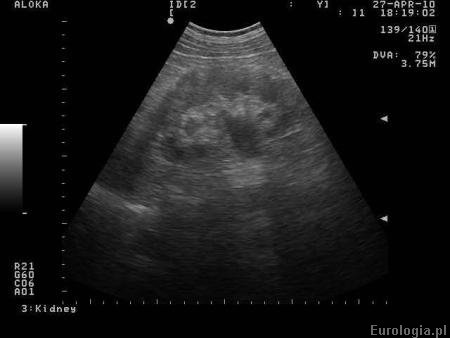

Fot. Poszerzony UKM nerki prawej w badaniu USG.

Zastój moczu w USG nerki oznacza, że obraz ultrasonograficzny sugeruje poszerzenie układu kielichowo - miedniczkowego nerki. UKM czyli układ zbiorczy zbudowany jest z systemu kielichów nwerkowych i miedniczki nerkowej. W warunkach prawidłowych UKM jest nieposzerzony. Zastój moczu wymaga weryfikacji w badaniach obrazowych w celu ustalenia przyczyny. Nie wiemy jakiego stopnia jest zastój oraz czy ma Pani jakiekolwiek dolegliwości. Nie wiemy co może być prawdopodobną przyczyną zastoju (zastosowanie Rowatinexu) sugeruje etiologiękamiczą) więc należy zaufać urologowi, który osobiście Panią zbadał i stwierdził, że 4 tygodnie nie wpłyną istotnie na funkcję nerki.